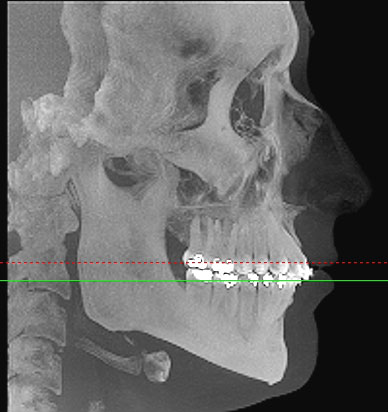

Im folgendem sehen Sie die Darstellung eines Teils des menschlichen Schädels mit Lokalisation des Nervkanales.

Sagittalansicht |